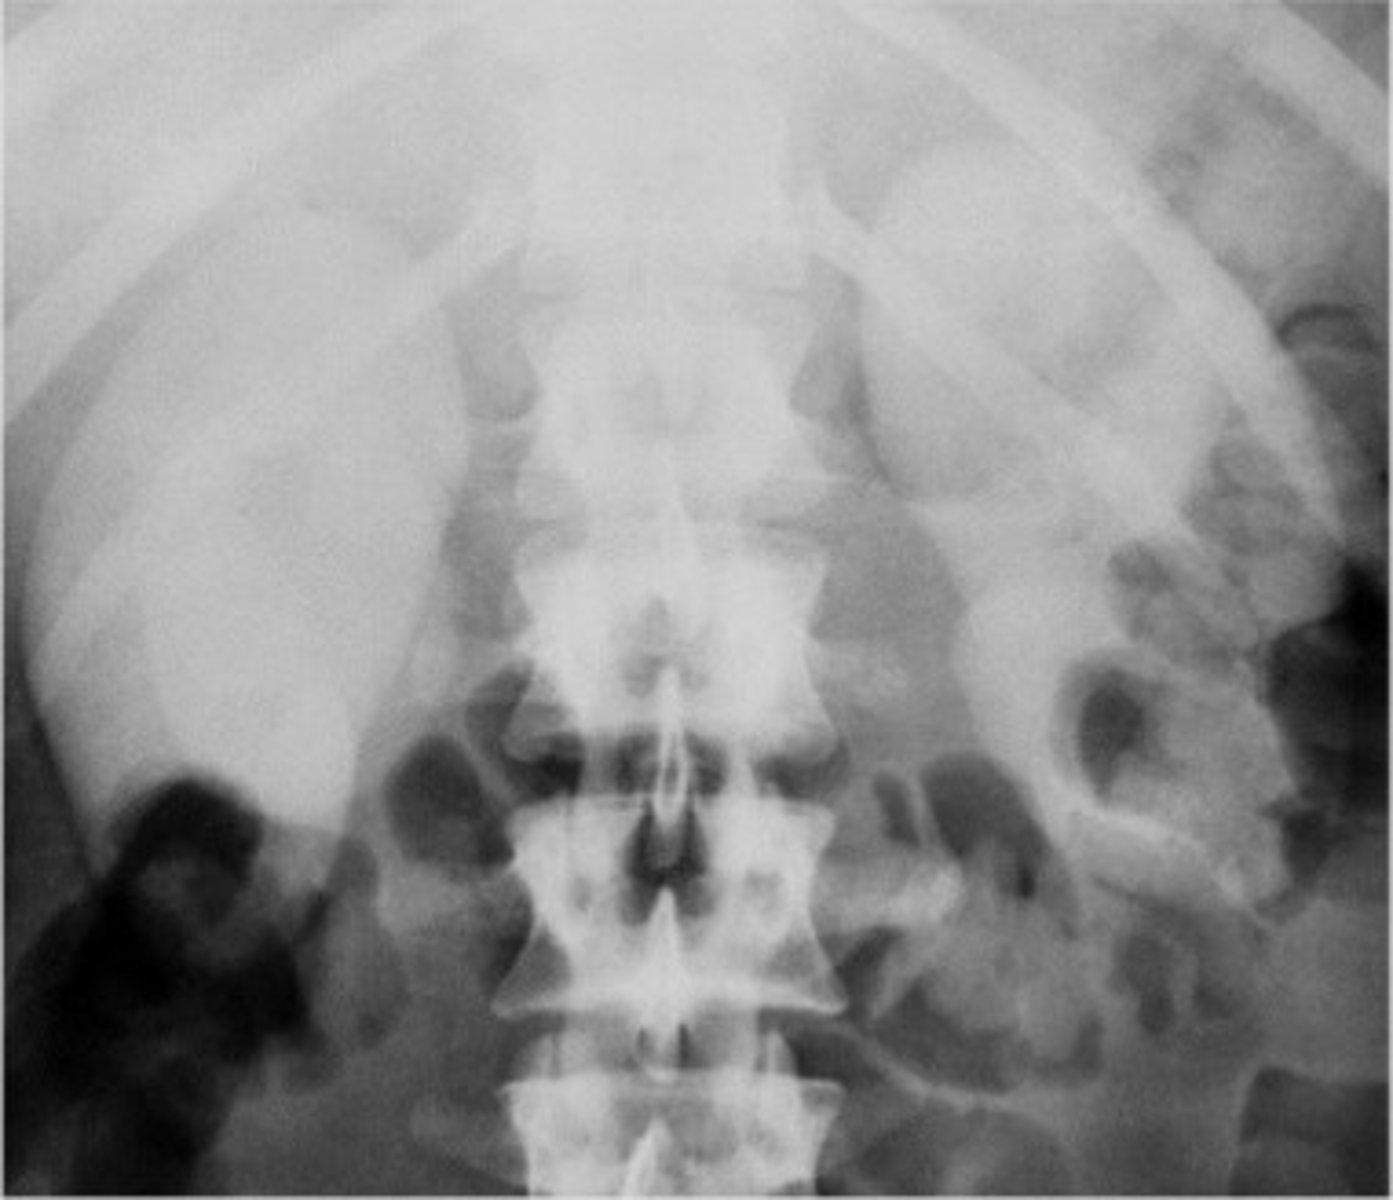

- Horseshoe Kidney

- Kidney stones

- What congenital anomaly occurs when the lower poles of the kidney fail to separate in the fetus and results in a horseshoe-shaped kidney?

- What can patients frequently develop because the ureters are displaced with this pathology?